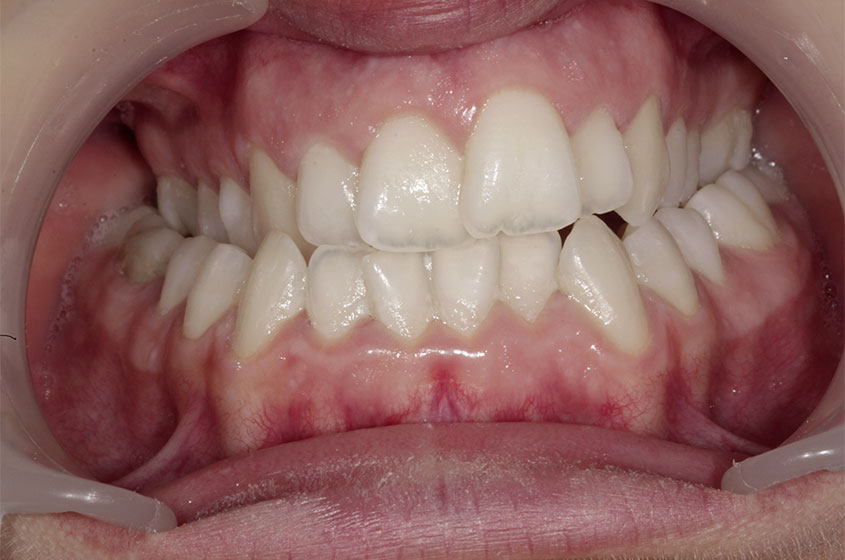

https://sorridibene.etweb.it/wp-content/uploads/2020/07/4-1.jpg

Inversione del morso posteriore

Se i denti dell’arcata superiore non chiudono correttamente e lateralmente e i denti inferiori sono più evidenti e sporg...